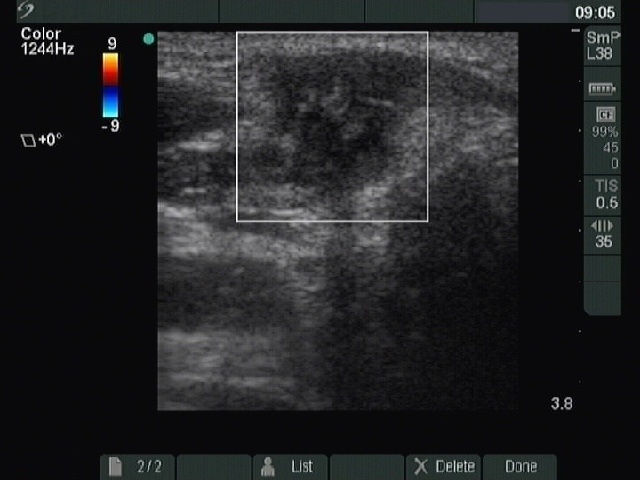

Granulation around surgical thread (histological diagnosis) - case 1386

This is a typical presentation of a granulation around surgical thread: a hypoechogenic, irregularly shaped, avascular mass having several echonormal areas corresponding to a ragged tissue.